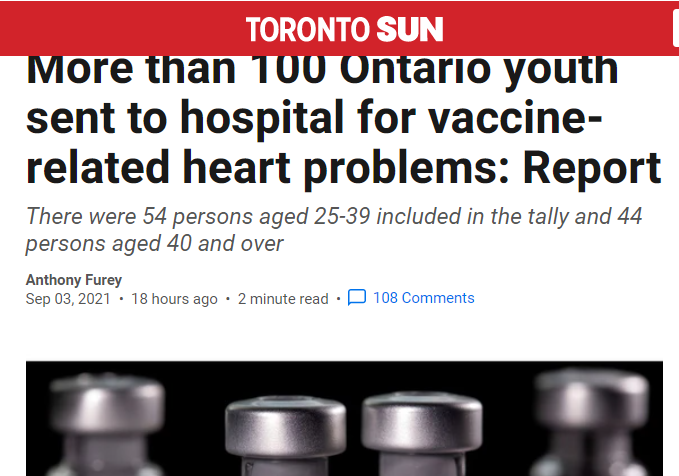

Από τις 7 Αυγούστου, αναφέρθηκαν 106 περιστατικά μυοκαρδίτιδας/περικαρδίτιδας στο Οντάριο, τη μεγαλύτερη σε πληθυσμό και η πλέον οικονομικά ανεπτυγμένη επαρχία του Καναδά, ηλικίας κάτω των 25 ετών. Αυτό είναι κάτι περισσότερο από το ήμισυ του συνόλου όλων αυτών των περιστατικών.

Σύμφωνα με την Υπηρεσία Δημόσιας Υγείας του Οντάριο (Public Health Ontario) 31 από αυτά τα περιστατικά αφορούσαν παιδιά ηλικίας 12 έως 17 ετών και 75 άτομα ηλικίας 18 έως 24 ετών. Η συντριπτική πλειοψηφία – το 80% – ήταν άνδρες.

Η έκθεση εξηγεί ότι η PHO εξέδωσε οδηγία τον Ιούνιο για τις μονάδες δημόσιας υγείας να αυξήσουν την παρακολούθηση αυτής της παρενέργειας μετά από αναφορές από τις Ηνωμένες Πολιτείες και το Ισραήλ για παρόμοιες ανησυχίες που εκτυλίσσονται σε αυτές τις χώρες.

Πιο συγκεκριμένα:

«Το ποσοστό αναφοράς μυοκαρδίτιδας/περικαρδίτιδας ήταν υψηλότερο μετά τη δεύτερη δόση εμβολίου mRNA από ό, τι μετά την πρώτη, ιδιαίτερα για εκείνους που έλαβαν το εμβόλιο Moderna ως δεύτερη δόση (ανεξάρτητα από το προϊόν που επιλέχθηκε για την πρώτη δόση)».